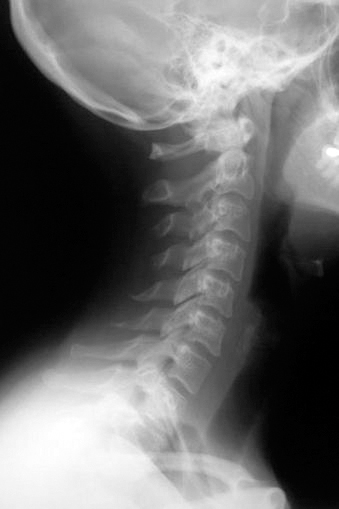

Так что шейный отдел позвоночника, состоящий из семи позвонков, должен иметь достаточную длину и определенную статику (рис. 1).

Рис. 1. Нормальная статика шеи. Правильный физиологический изгиб: А=А1

А что в действительности имеем мы? Даже здоровый позвоночник (хотя где его найдешь?) с возрастом деформируется, «проседает», меняет статику. Появляется симптом смещенной вперед и запрокинутой назад головы (рис. 2).

Рис. 2. Гиперлордоз шейного отдела позвоночника: B > B1

В результате небольшой физиологический изгиб гипертрофируется, и шейные позвонки «проваливаются» вглубь шеи. Особенно интенсивно это происходит при «сидячей» работе. Формируется гиперлордоз шейного отдела позвоночника. Чаще всего виной тому становится не возраст, не тяжесть гравитации, а попросту плохая осанка. При сутулости попытка смотреть в глаза собеседника достигается запрокидиванием головы назад, сопровождающимся взглядом исподлобья. Бывает, посмотришь на женщину – лицо еще молодое, видно, что она ухаживает за собой. А взглянешь издали – прямо старушка ковыляет: ссутулилась, шейка вперед подалась, плечики сжались. Хорошо, сама себя не видит, а то бы очень огорчилась.

Из-за того, что с возрастом диски между позвонками уплощаются, шея укорачивается, часто весьма значительно (рис. 3).

Рис. 3. Шейный отдел позвоночника

Рис. 4. Нормальный физиологический лордоз шейного отдела позвоночника

Проблемы статики шейного отдела не ограничиваются возрастным гиперлордозом, когда позвонки проваливаются вглубь шеи (рис. 5). Часто, наоборот, этот изгиб может быть излишне спрямлен (рис. 6).

Рис. 5. Гиперлордоз шейного отдела позвоночника